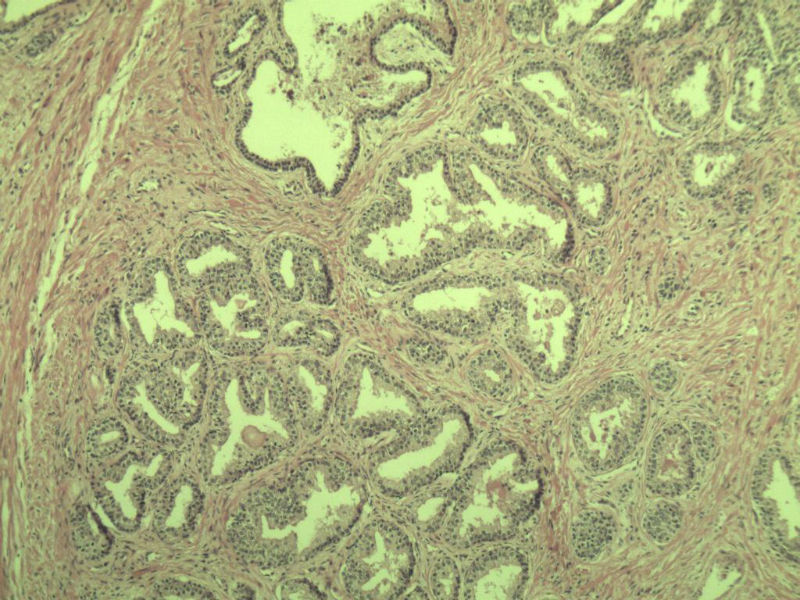

男 75岁 因排尿困难半年行前列腺切除术,体积 4 × 3 × 2.5 cm3,切面灰白,实性,质韧。请各位老师看看 有问题没? 谢谢了!

高级别上皮内瘤变,建议免疫组化:P63、34BE12、P504S

前列腺增生症伴鳞化

良性前列腺增生

良性前列腺增生伴尿路上皮化生

前列腺增生伴尿路上皮鳞化及Brown巢形成,未见恶性。